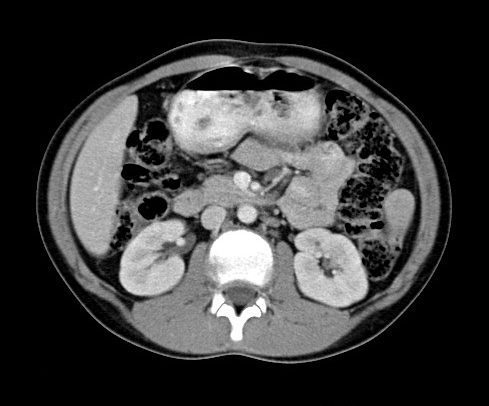

Since the 1970s, computed tomography (CT) has

revolutionized medical screening, diagnostics, and treatment with its ability

to non-invasively image the human body. Figure 1 shows a typical CT image of a

human abdomen [1] and clearly illustrates structures such as the liver,

kidneys, and spine.

Figure 1. Typical abdomen CT image.